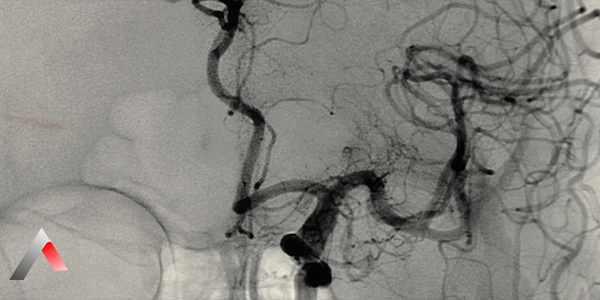

• Serebral (Beyin) Anjiyografi Beyin damar ağının en ince ayrıntısına kadar haritalanması işlemidir. Azurion Avantajı: Dijital Subtraksiyon Anjiyografi (DSA) özelliğiyle kemik dokusunu görüntüden temizleyerek sadece damarları kristal netliğinde sunar.

• Serebral Anjiyografi Beyin damar ağının en ince ayrıntısına kadar kristal netliğinde görüntülenmesi.